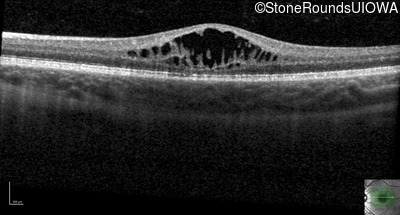

XL Retinoschisis (IIIB1)

Age at visit: 7 years

This 7 year old boy failed a vision screening test at his pediatrician 5 months ago.